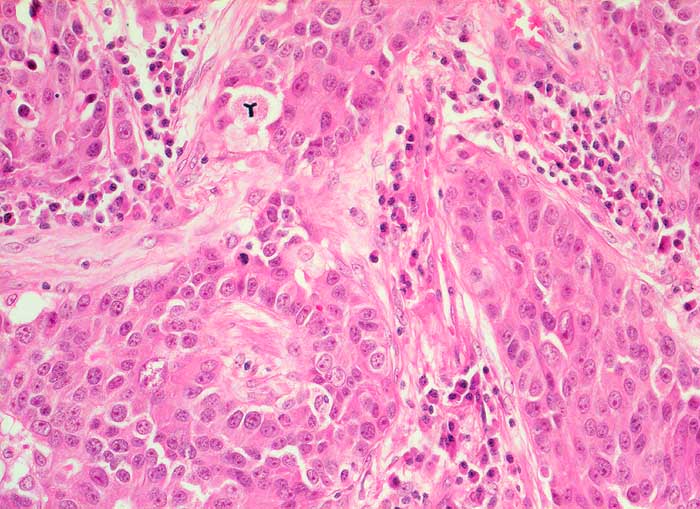

Seminommetastase

maligner Tumor

Lunge

Solide Tumorzellstränge umgeben von plasmozellulär infiltriertem Stroma. Grosse Tumorzellen mit reichlich eosinophilem Zytoplasma und vesikulären Kernen mit prominenten Nukleoli. Atypische Mitose (Mercedesstern).

Lungenrundherd. Status nach Semikastration wegen Seminom.

200